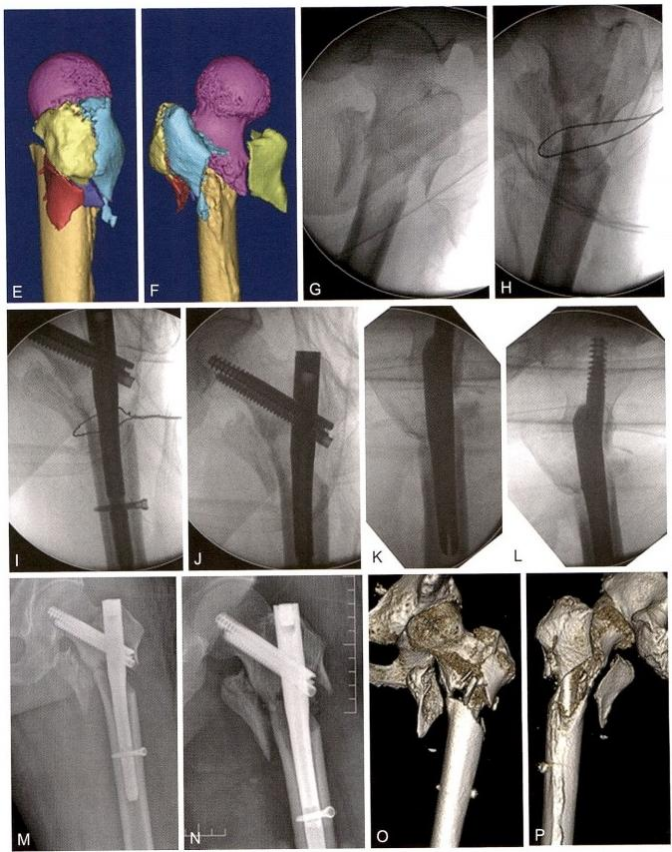

3)术中复位技巧3:点状复位钳钳夹固定(冠状位股骨转子间骨折)。 股骨大转子骨折线从前上方向后下方延伸,臀中肌的大部分位于近断端,臀中肌的前份在大转子的止点位于远断端,后方软组织铰链破裂,呈现骨折端后方张口,股骨颈及相连的大转子大部呈现极度外旋(图 9-10A 、B 、C)。先将远端外旋牵引,同时用点状复位钳钳夹,使骨折后方张口复位,然后经大转子后方植入克氏针,改内旋、内收牵引,在大转子顶点插入 导针,常规开口扩髓,植入主钉和螺旋刀片(图9-10)。

图9-10 点状复位钳夹固定。 A.术前X 线 ;B. 术前CT 正位;C. 术前CT 侧位;D. 钳夹复位后侧位透视